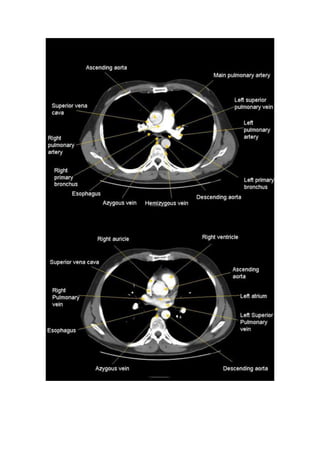

B) ANATOMÍA MEDIASTÍNICA.

Es la zona situada entre los dos pulmones y está limitada por la pleura parietal medial.

Contiene las estructuras cardiovasculares centrales, traqueobronquiales y el esófago.

Todo ello envuelto en grasa y rodeado de una gran cantidad de pequeños ganglios

linfáticos.

Para efectos docentes dividiremos el mediastino en tres compartimentos (según Felson).

1. mediastino anterior (prevascular)

2. mediastino medio (vascular)

3. mediastino posterior (postvascular)

Esta división del mediastino corresponde a regiones fácilmente reconocibles en la

proyección lateral del tórax.

Para comprender mejor la anatomía radiologica de la placa simple del tórax vamos a

estudiar la anatomía del tórax en el plano axial con cortes axiales en ventana de

mediastino o también llamada de partes blandas. En esta ventana no vamos a ver los

pulmones que quedan totalmente ocultos. Veremos muy bien el mediastino con sus

estructuras vasculares y su grasa así como los ganglios linfáticos que están en él.

También veremos muy bien las partes blandas de la caja torácica. Aunque el hueso

queda bien evidendente esta ventana no sirve para evaluar alteraciones óseas. Para ello

tendríamos que usar una ventana más adaptada para ver claramente el hueso y sólo el

hueso.